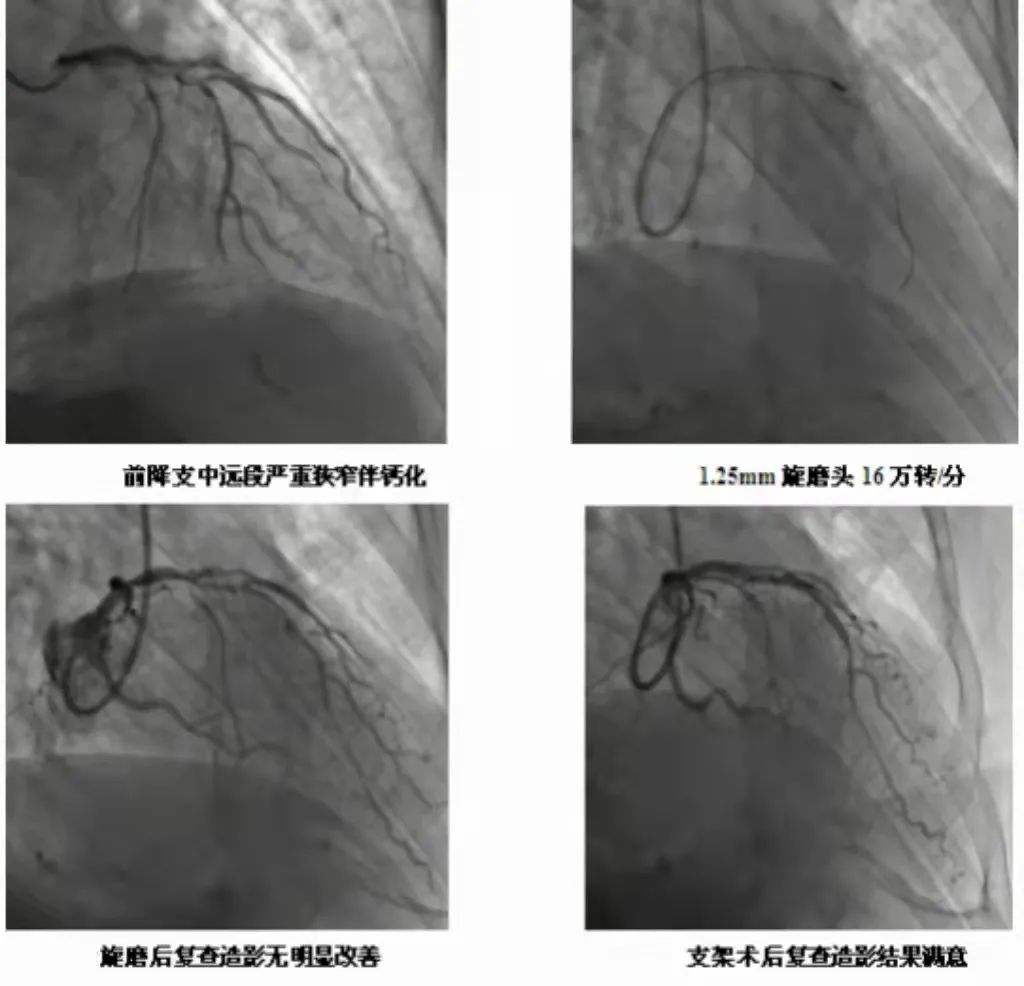

3月4日,辽阳市中心医院心血管五病房成功完成2例冠状动脉旋磨术,为严重血管钙化患者顺利植入支架。

患者主因"阵发性胸闷"就诊中心医院心血管五病房,诊断为不稳定型心绞痛。冠脉造影显示患者冠状动脉狭窄分别为90%、85%,伴钙化严重。严重的血管钙化使冠脉支架通过困难及支架膨胀不良等情况。

那么钙化严重的血管能不能做支架?赵丽君主任带领的冠脉介入团队,深知对冠状动脉钙化患者行PCI手术是介入治疗的难题之一,成功率低。但患者的病情又亟需实施介入治疗。为此,赵丽君主任仔细分析病情,制定手术策略,对钙化的病变血管做好支架植入治疗前的预处理工作,为钙化的血管行冠状动脉旋磨术,通过差异性切割原理,将钙化病变打磨,最终顺利植入支架,解决了严重钙化病变支架植入的治疗难题。